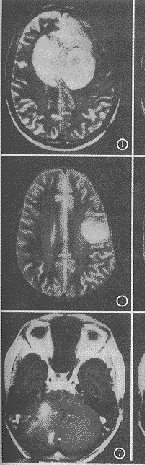

图1~3 男,54岁,星形胶质细胞瘤Ⅲ级。肿瘤侵犯双侧额顶叶,胼胝体膝部。T1,T2加权肿瘤边缘清楚,信号不均匀,可以看到呈粗大条状低信号区的肿瘤血管及出血。增强肿瘤信号不均匀,增强程度明显。

图4~6 男,35岁,星形胶质细胞瘤Ⅰ级。肿瘤侵犯左侧顶叶。T1加权肿瘤边缘不清楚,信号均匀,没有看到肿瘤血管和出血。增强后肿瘤信号均匀,增强程度轻。

图7~9 女,65岁。星形胶质细胞瘤Ⅱ级。肿瘤侵犯右侧小脑。T1、T2加权肿瘤边缘不清楚,信号不均匀,没有看到肿瘤血管和出血。增强后肿瘤信号不均匀,增强程度中。

文献报道,MRI的表现和肿瘤的恶性程度有关[2,14,15]。Ⅰ级星形胶质细胞瘤为良性肿瘤。本研究之本组资料显示肿瘤多侵犯单个部位94.44%,MRI信号多均匀(88.88%),占位效应轻微94.44%,瘤内无血管和出血,增强后扫描显示轻度增强为主(77.77%),而且信号均匀77.78%(图4~6)。Ⅲ~Ⅳ级星形胶质细胞瘤是恶性肿瘤。本研究的本组肿瘤侵犯多个部位占56.66%,信号不均匀占73.33%,占位效应明显占50.00%,瘤内血管出现占56.66%,瘤内出血见33.33%,增强后扫描明显强化者占73.33%,不均匀增强占93.33%(图1~3);Ⅱ级星形胶质细胞瘤则介于两者之间(图7~9)。